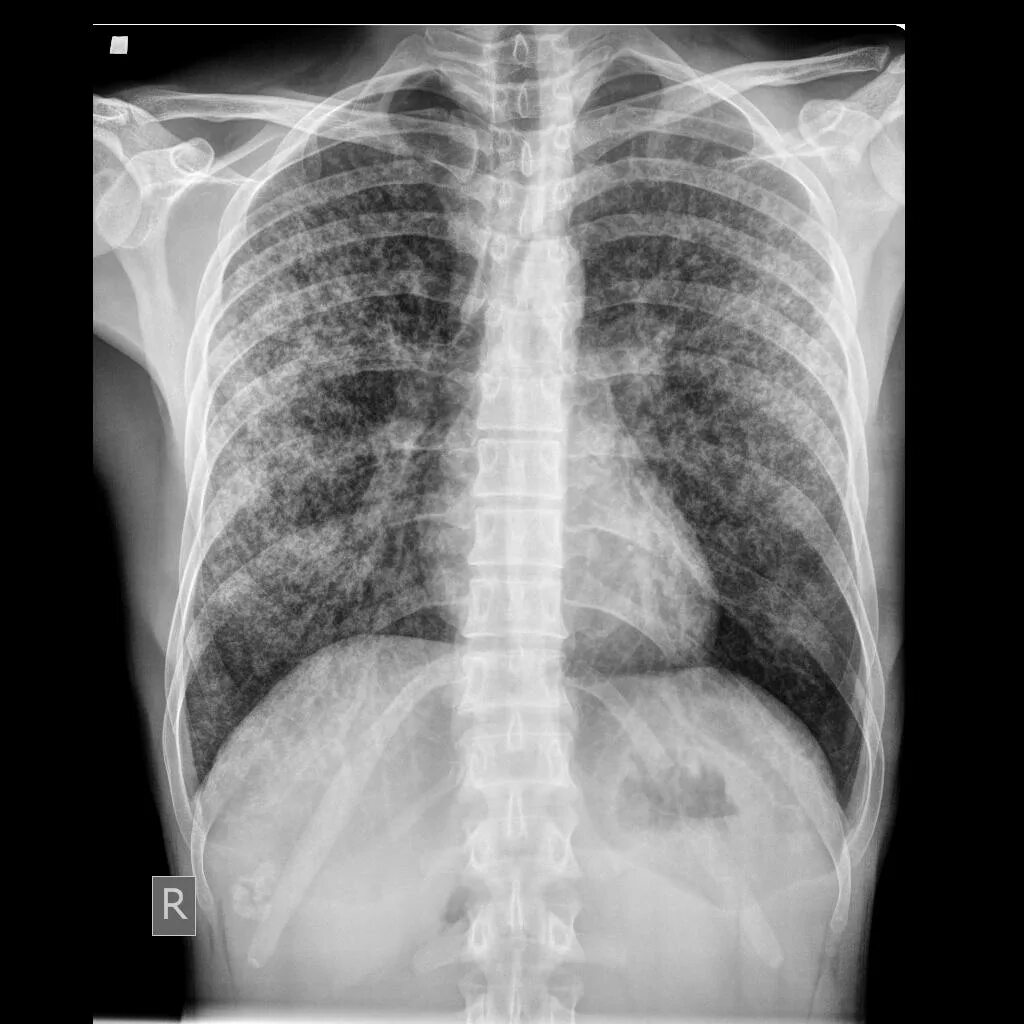

Скате легких